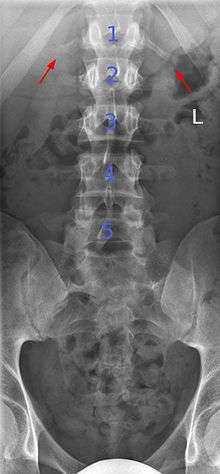

Transitional vertebrae

Transitional vertebrae have the characteristics of two types of vertebra. The condition usually involves the vertebral arch or transverse processes. It occurs at the cervicothoracic, thoracolumbar, or lumbosacral junction. For instance, the transverse process of the last cervical vertebra may resemble a rib. A transitional vertebra at the lumbosacral junction can cause arthritis, disk changes, or spinal cord compression. Back pain associated with lumbosacral transitional vertebrae (LSTV) is known as Bertolotti's syndrome. One study found that male German Shepherd Dogs with a lumbosacral transitional vertebra are at greater risk for cauda equina syndrome, which can cause rear limb weakness and incontinence.[6]